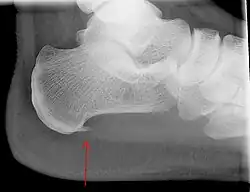

An incidental finding associated with this condition is a heel spur, a small bony calcification on the calcaneus (heel bone), which can be found in up to 50% of those with plantar fasciitis.[6] In such cases, it is the underlying plantar fasciitis that produces the heel pain, and not the spur itself.[13] The condition is responsible for the creation of the spur, though the clinical significance of heel spurs in plantar fasciitis remains unclear.[12]

Imaging

Medical imaging is not routinely needed. It is expensive and does not typically change how plantar fasciitis is managed.[15] When the diagnosis is not clinically apparent, lateral view X-rays of the ankle are the recommended imaging modality to assess for other causes of heel pain, such as stress fractures or bone spur development.[7]

The plantar fascia has three fascicles-the central fascicle being the thickest at 4 mm, the lateral fascicle at 2 mm, and the medial less than a millimeter thick.[19] In theory, plantar fasciitis becomes more likely as the plantar fascia's thickness at the calcaneal insertion increases. A thickness of more than 4.5 mm ultrasound and 4 mm on MRI are useful for diagnosis.[20] Other imaging findings, such as thickening of the plantar aponeurosis, are nonspecific and have limited usefulness in diagnosing plantar fasciitis.[13]